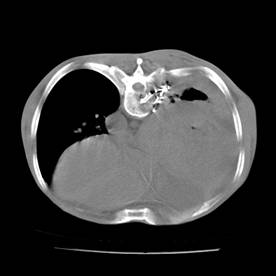

典型病例2:患者张XX,男,65岁,住院号:496686,因发热、胸闷、背痛2月余入院,体温最高达39℃,背部疼痛难忍。2015年6月29日胸部增强CT示:右肺下叶11.6cmx12.5cm巨大肿块,中心大片低密度坏死区,第8胸椎及右侧第8后肋骨转移。于7月2日行CT引导下穿刺活检术,病理证实为右肺鳞癌。给予125I放射性粒子植入治疗,术中首先利用植入针,穿刺肿块中央坏死区,连接引流袋后抽出肿瘤内坏死液体约500ml,抽液后肿瘤缩小约1/3;随后将125I粒子植入到第8胸椎体及第8后肋骨转移区,同时重点放置患侧滋养动脉供血区域。术后第二天,患者体温恢复正常;术后一周随访,患者背痛缓解。该患者出院回家,仍在随访中。

术中抽液

术中粒子植入